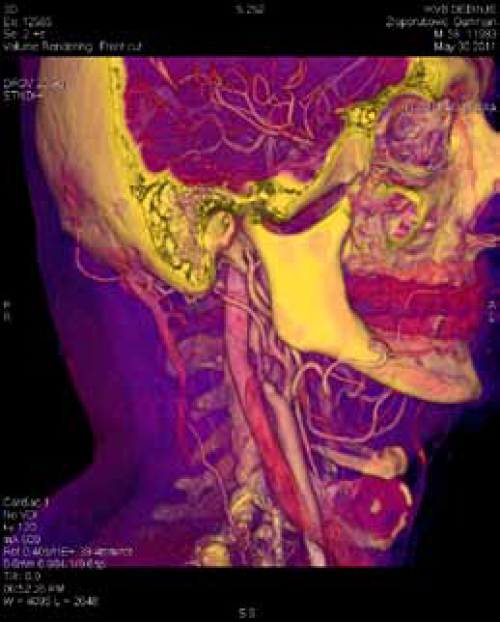

Multislice Computed Tomography Angiography (MSCT) ili Multidetector Computed Tomography (MDCT) karotidnih arterija značajno skraćuje vreme trajanja pregleda, količinu zračenja i kontrastnog sredstva, daje manje artefakata i pruža mogućnost kvalitetne 3D rekonstrukcije. Danas, posle više generacija MSCT aparata možemo reći ovi nalazi imaju brojne prednosti u poredjenju sa konvencionalnom angiografijom.

MSCT angiografija pokazuje stepen stenoze i prirodu plakova, ali i morfologiju karotidnih arterija i odnos sa ostalim strukturama vrata, kao i Willisov poligon. Neophodno je planiranje rekonstruktivnih zahvata trastorakalnim putem. MSCT 3D tehnikom se prikazuju morfološke promene karotidnih arterija u vidu angulacija, elongacija, kinkinga i coilinga. Prisustvo prizidne tromboze se može naslutiti arteriografski, a videti Duplex-sonografski i MSCT-om.

Skoro potpuna okluzija brahiocefaličkog trunkusa sa dugačkom totalnom trombozom zajedničke karotidne arterije levo

MSCT karotidna angiografija pruža mogućnost istovremenog sagledavanja karotidnih i drugih arterija koja koje ishranjuju mozak, ali i moždanog parenhima kao cerebralnog venskog sistema.